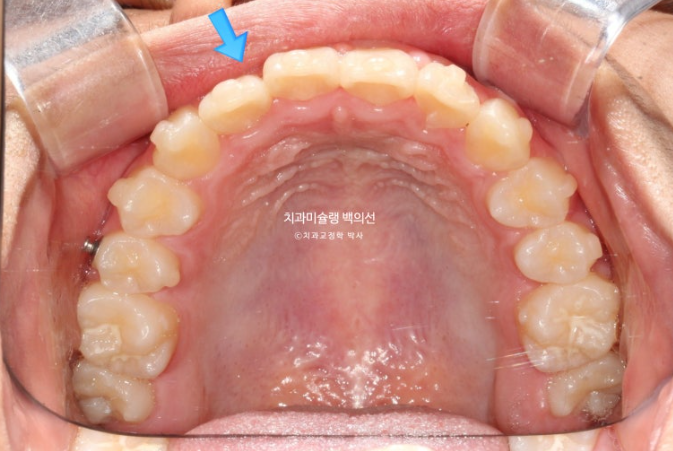

24년 1월 교정치료를 위해 온 만 10세 어린이 입니다.

3년 전에 소아치과에서 앞니 부분교정을 한 적이 있다고 합니다.

그래서 위 앞니에는 중절치 두 개를 잇는 철사유지장치가 붙어있었습니다.

중심선이 약 2mm 어긋나 있으며 위 앞니 치축은 한쪽으로 기울어져 있습니다.

앞니가 깊게 물리는 과개교합도 보입니다.